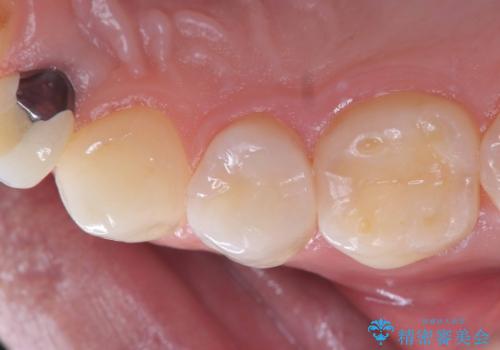

- 「2か月前から歯に違和感があるので診て欲しい」を主訴に来院された患者様です。

被せ物がコア(土台)ごと取れておりかつ根っこも折れてしまっている(歯根破折)状態でした。

歯根破折により保存は不可と診断し抜歯後、骨ができるのを待ってインプラントで治療を行いました。

メタルコアは度々歯根破折の原因になります。なので現在はファイバーコアが主流となっています。